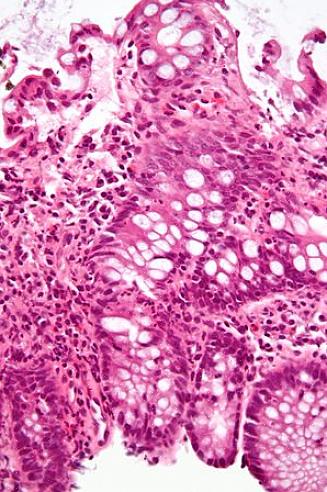

קוליטיס כיבית

קוליטיס כיבית משפיעה רק על המעי הגס. עם זאת, הדלקת מתחילה בפי הטבעת, מה שנקרא מעורבות פי הטבעת. הדלקת משפיעה רק על הממברנה, שהיא הגורם המבדיל הגדול ביותר ממחלת קרוהן.

מחלת קרוהן: מחלות מעיים

מחלת קרוהן יכולה להשפיע על כל חלק של מערכת העיכול, מהפה ועד לפי הטבעת. ברוב המקרים, הדלקת מתרחשת סביב המעי הדק. בניגוד למקרים של קוליטיס כיבית, הדלקת משפיעה על כל דופן המעי ולא רק על הקרום.